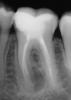

Yulechka1986 Опубликовано 6 января, 2013 Поделиться Опубликовано 6 января, 2013 36 зуб моей медсестры. Девушке 20 лет, полгода назад беспокоили сильные ноющие боли, спасалась кеторолом, "само прошло".. не обращалась. Зуб лечен по поводу пульпита в 16 лет. Сейчас практически не беспокоит, искали с ней какой зуб реагирует на сладкое - нашли пружинку. В нашем городе микроскопистов нет, как считаете на выход зуб или пробовать бороться. Ссылка на комментарий

д-р Вит Опубликовано 7 января, 2013 Поделиться Опубликовано 7 января, 2013 ИМХО зуб средней степени сложностимикроскоп тут не обязателен,достаточно обычной оптики(3-3.5)можно даже не пытаться вытаскивать лентуло,отбайпасить ,откалиброватьпри ирригации отломок вылетит,а нет хоронить в гуттезы лучше через кальций,возможно пару раз(ИМХО Ссылка на комментарий

Снежана Опубликовано 7 января, 2013 Поделиться Опубликовано 7 января, 2013 конечно сохраняйте, тем более ваша медсестра. даже если у вас никак не получится извлечь или обойти инструмент. отмойтесь несколько раз, подержите с кальцием и обтурируйте. есть вероятность уменьшения очага при пройденном полностью и обработанном 1 канале в медиальной системе. Ссылка на комментарий

Каплан Опубликовано 8 января, 2013 Поделиться Опубликовано 8 января, 2013 Юля, обязательно постарайтесь. И вам попытка, и медсестре скорее всего зуб сохраните. 1. открыть зубик, отмыть дистальную систему и один медиальный.дистальных судя по всему два. и сходятся.2. если на это все ушло не больше часа +- 15 минут, то отмыть все до пружинки, файлами не дальше 40 номера до пружинки. дальше рядышком пройти 10кой постараться. этого для первого визита боле чем хватит. не мучайте дольше 2х часов. (исключение- если реально поймете что почти достали). если не успеете за два часа дойти до пружинки - кальций и временную и след..визит. насчет оптики - не уверен что она очнь поможет - скорее всего будет не видно, разв что снести медиальную стенку и разбабахать канал. осторожнее с малой кривизной... и очень осторожно с работой по большой кривизне... а то получите такую картинку http://forum.stom.ru/topic/19827-%d1%81%d0%b0%d0%bc-%d0%bf%d0%be%d0%bb%d0%be%d0%bc%d0%b0%d0%bb-%d1%81%d0%b0%d0%bc-%d0%b4%d0%be%d1%81%d1%82%d0%b0%d0%b2%d0%b0%d0%b9-%d0%bf%d0%b5%d1%80%d0%b2%d0%b5%d0%bd%d0%b5%d1%86/page__hl__%2B%D1%81%D0%B0%D0%BC+%2B%D0%B4%D0%BE%D1%81%D1%82%D0%B0%D0%B2%D0%B0%D0%B9 1 Ссылка на комментарий

johniola Опубликовано 9 января, 2013 Поделиться Опубликовано 9 января, 2013 думаю можно спасти,только надо поработать. вот аналогичный случай хотя лентуло доставать легче.mm.bmp4.01.2013.bmp214.bmp Ссылка на комментарий